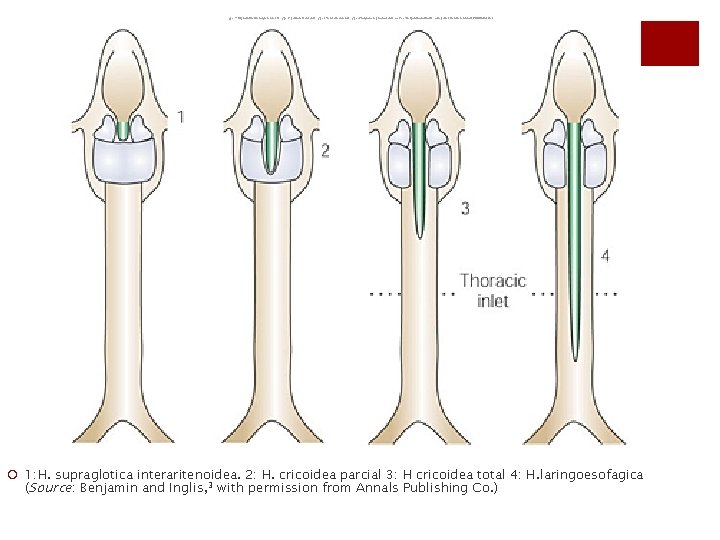

Type 1: supraglottic interarytenoid cleft. Type 2: partial cricoid cleft. Type 3: total cricoid cleft. Type 4: laryngoesophageal cleft. (Source: Benjamin and Inglis, 3 with permission from Annals Publishing Co. ) ¡ 1: H. supraglotica interaritenoidea. 2: H. cricoidea parcial 3: H cricoidea total 4: H. laringoesofagica (Source: Benjamin and Inglis, 3 with permission from Annals Publishing Co. )